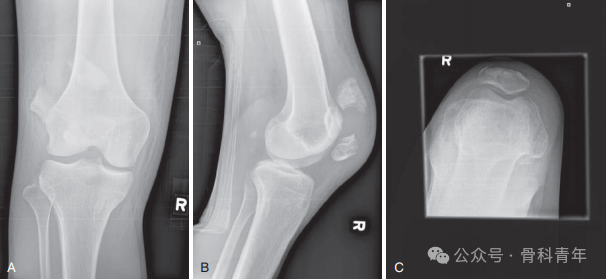

“克氏针张力带技术”是治疗髌骨横行骨折的最经典技术。